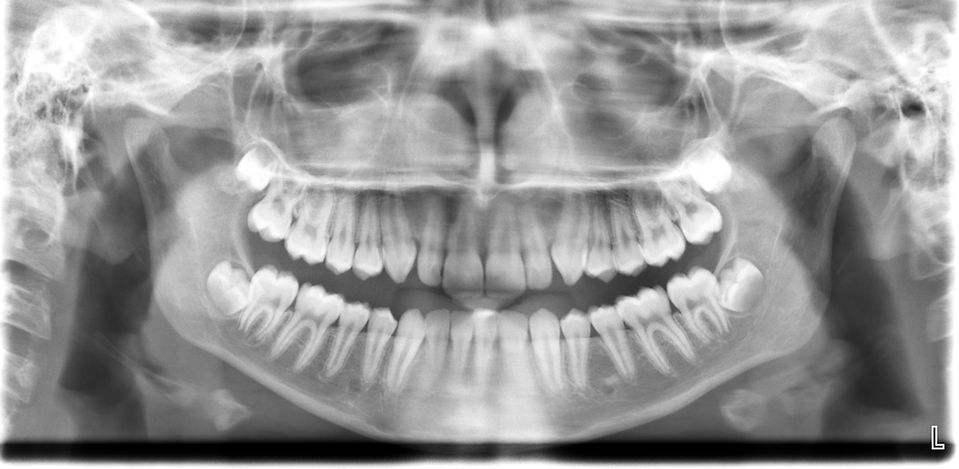

A panoramic X-ray captures a full view of all the teeth, jaws, and surrounding structures in a single image. The AAPD recommends a panoramic X-ray at two key ages. At age 6, it helps assess proper jaw growth and development, and allows us to check for missing, extra, or impacted teeth, as well as the presence of cysts or tumors in the jaws. At age 16, it helps determine whether wisdom teeth need to be removed.